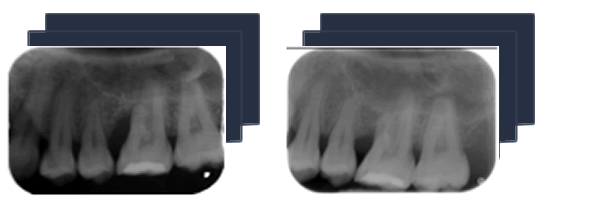

Die Erkrankung verläuft in den meisten Fällen ohne Beschwerden ab und sie hat mehrere Ursachen. Daher hat die Früherkennung eine große Bedeutung und die Therapie erfolgt meist ganzheitlich und interdisziplinär entsprechend den individuellen Ursachen. Im Gespräch und Befund spielen daher neben den Standarduntersuchungen wie Ausmessen der Zahnfleischtaschen, Röntgenbefund und Mundhygienebeurteilung auch Themen wie z.B. Rauchen, Ernährung und Allgemeingesundheit eine Rolle.

Bei einer Parodontitis kommt es zu Knochenabbau und zur Bildung sogenannter Zahnfleischtaschen. Diese misst der Zahnarzt mit einer speziellen, stumpfen Parodontalsonde millimetergenau aus. Zusätzlich wird mithilfe verschiedener Index-Systeme der Entzündungsgrad des Zahnfleisches beurteilt und gezielt nach Nischen gesucht, in denen sich Bakterien ansiedeln können.